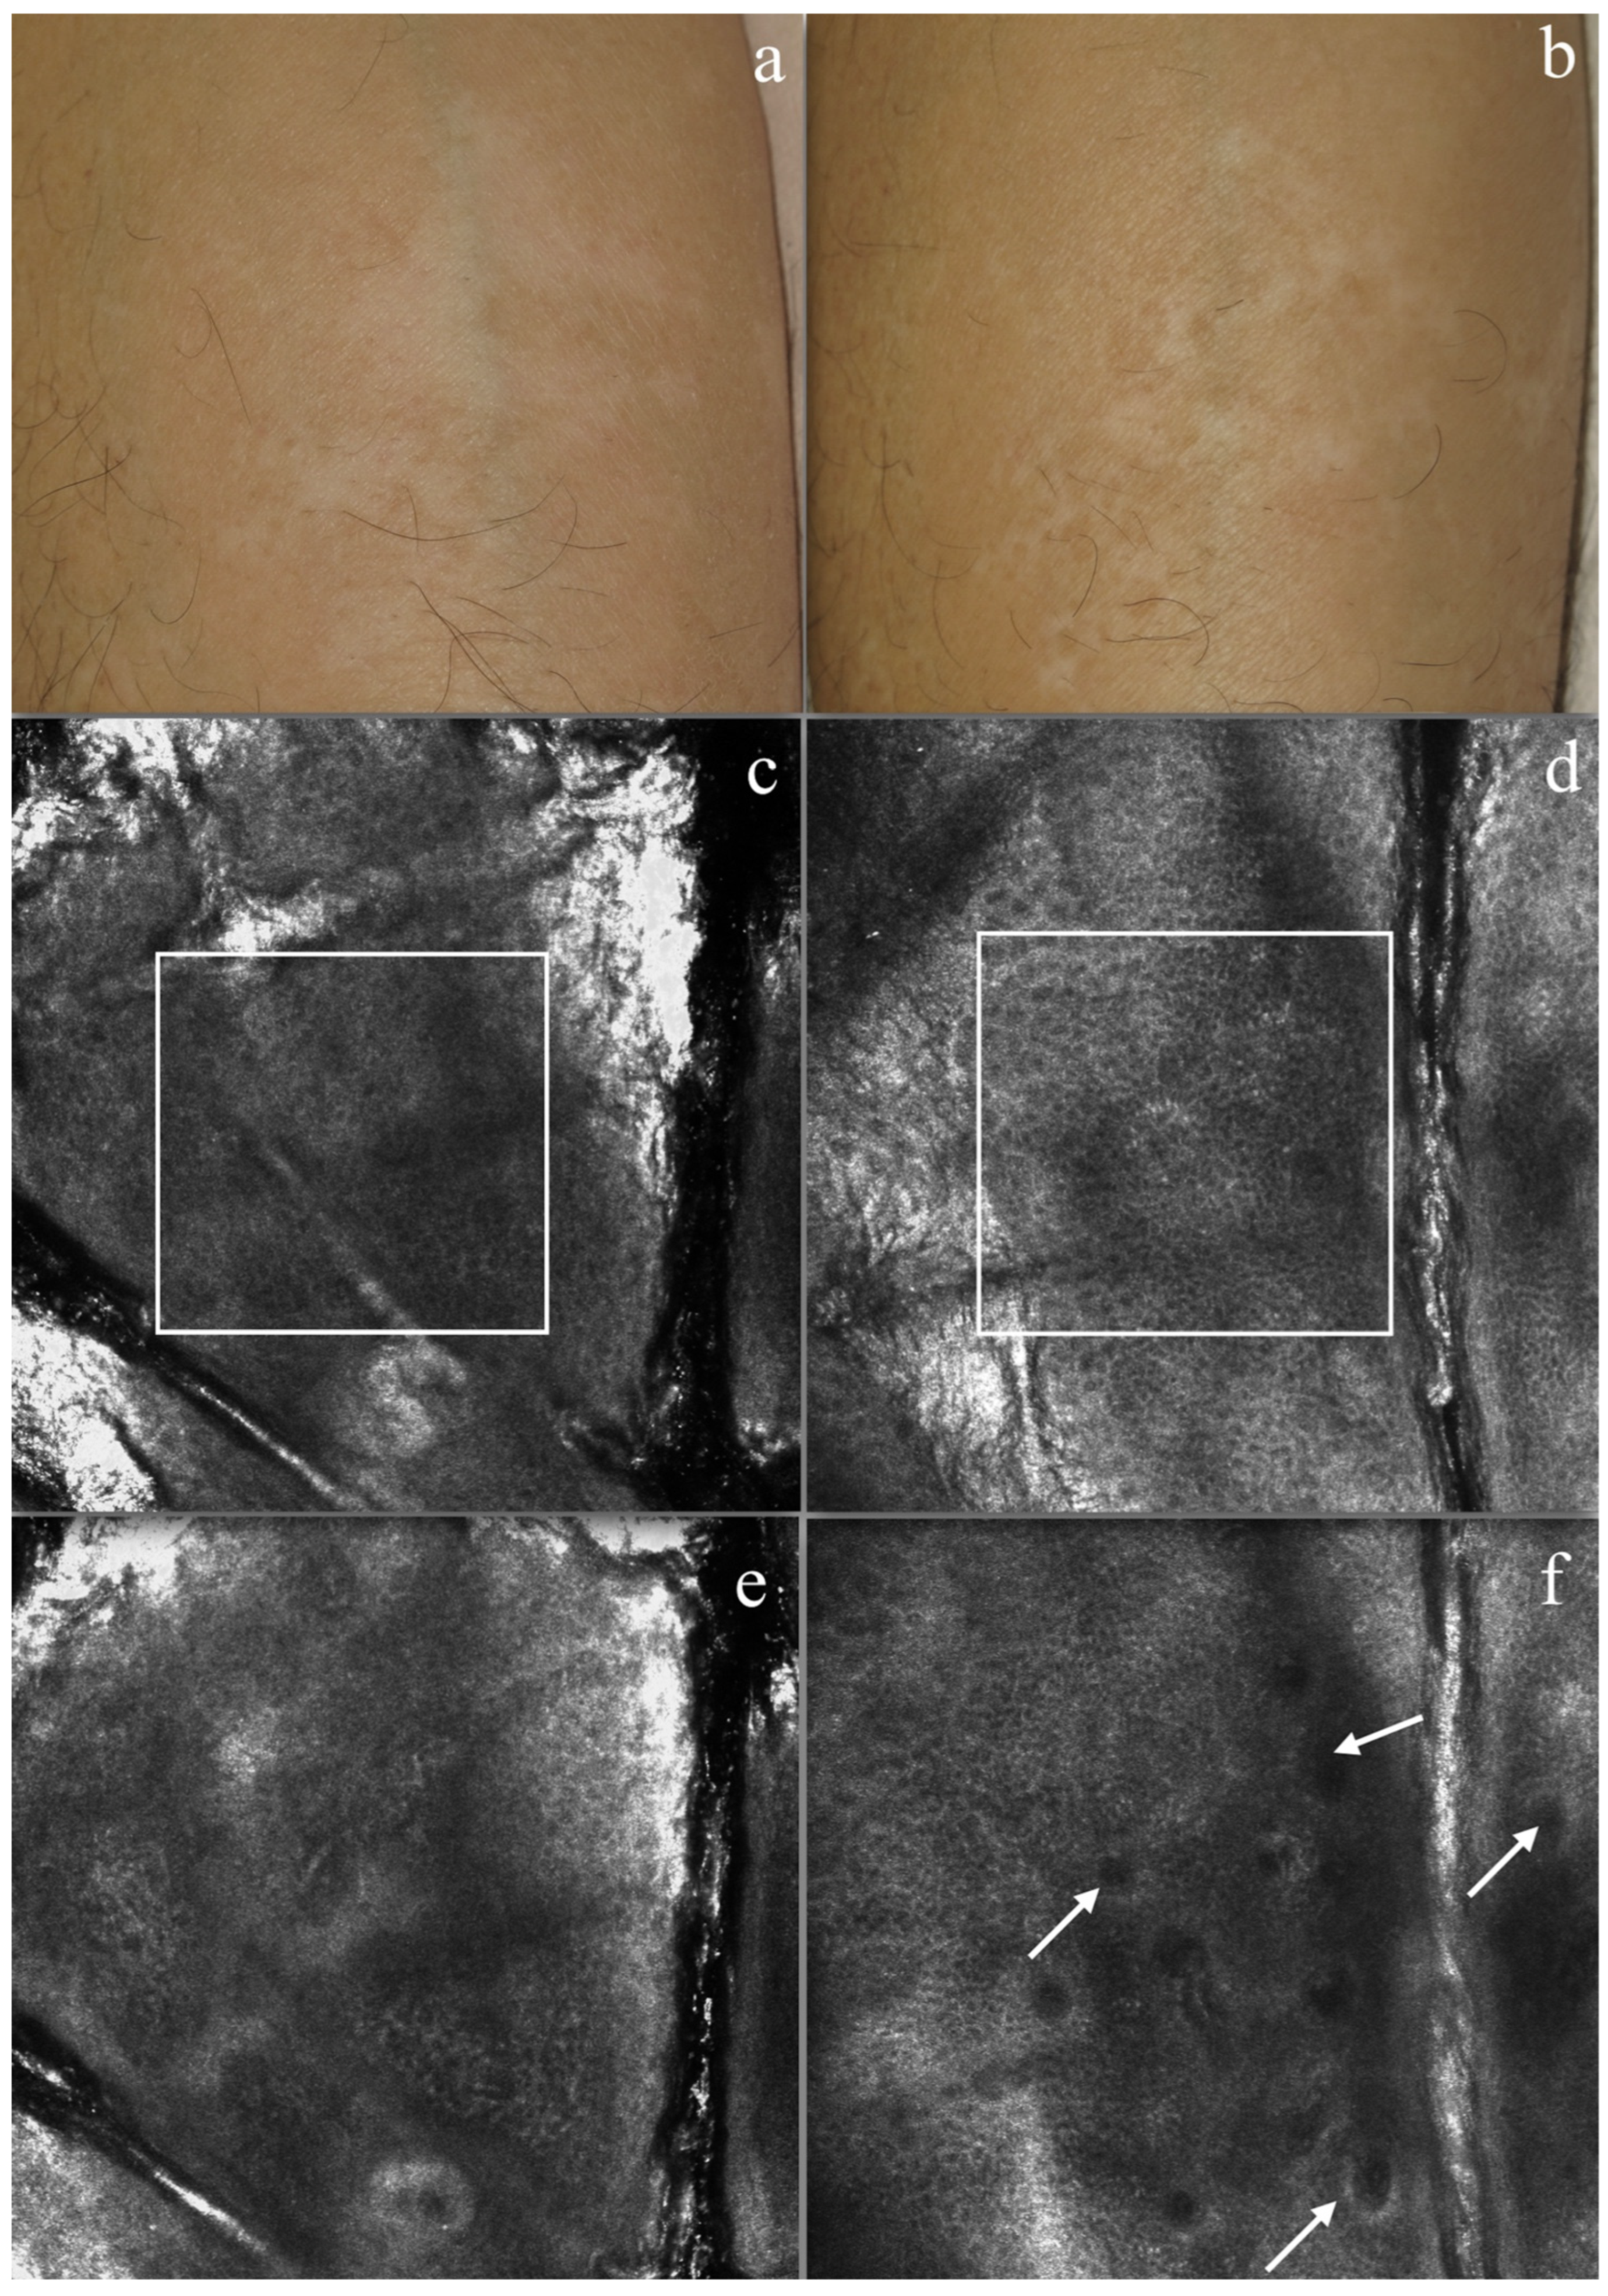

3.2. RCM Evaluation